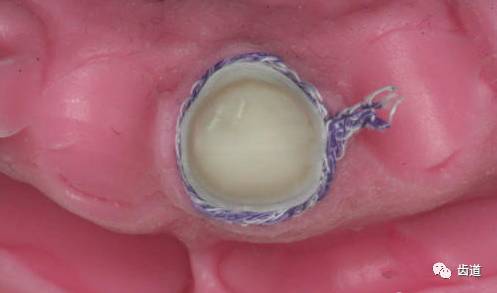

二次排龈

从一次排龈的对侧开始,仅将龈线的一半压入龈沟

从外侧向内侧拧入,360度排龈回到起点

可以预留少许,便于提出。

取印膜.在提出第二根排龈线的同时(第一根排龈线仍留在龈沟内},迅速将高流动性硅橡胶龈膜材注入龈沟,时间是关键.